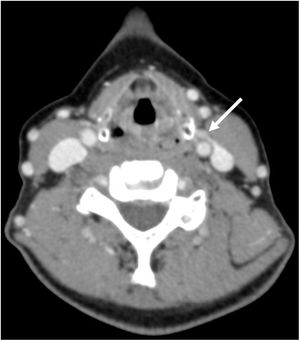

Se realizó una paratiroidectomía selectiva en el 46,9% (30/64) de la muestra y una exploración cervical bilateral en el 51,7% (34/64) restante. Un 9,4% de los casos (6/64) fueron debidos a una glándula de localización ectópica (fig. 1). Las complicaciones presentadas fueron cinco casos (7,8%) de hipoparatiroidismo transitorio y un caso (1,6%) de infección de herida quirúrgica, sin que se recogieran complicaciones en relación con el nervio laríngeo recurrente ni otras complicaciones definitivas.

En este contexto, la tomografía computarizada en cuatro dimensiones (TC-4D) es un estudio de localización preoperatorio que consiste en la adquisición de tres fases vasculares (basal, arterial y venosa), valorando el comportamiento de las lesiones en función del tiempo tras la administración del contraste intravenoso8. En esta prueba, la rápida captación y el rápido lavado del contraste son diagnósticos del adenoma de paratiroides8, lo que se combina con la alta resolución espacial de la TC para localizar la glándula patológica9. Esta prueba de localización ofrece una buena sensibilidad para la lateralización de la lesión, cercana al 81% (intervalo de confianza [IC] 95%: 75-87), mientras que la sensibilidad para la localización en el cuadrante adecuado es del 73% (IC 95%: 69-78)10.